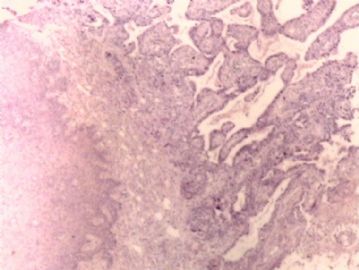

腺鳞癌?

姓    名: ××× 性别:   年龄:  39岁

标本名称:  宫颈活检

简要病史:  同房出血3次,tct HSIL

考虑:原位腺癌,小灶性区域有鳞状上皮向间质内浸润,考虑有鳞状细胞癌结构。